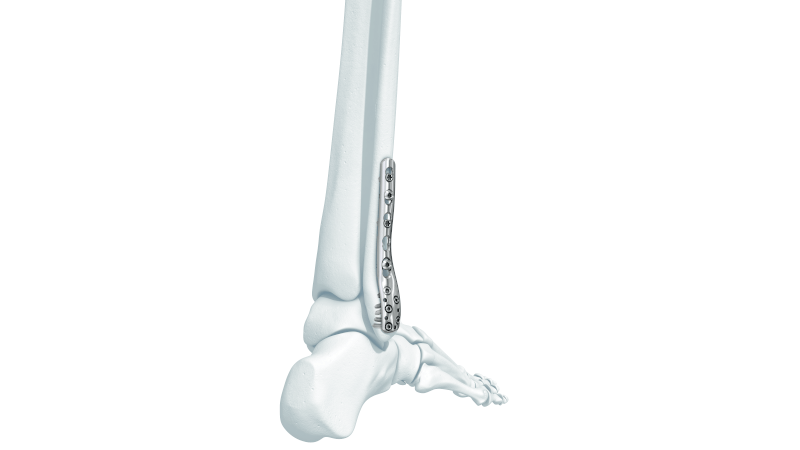

- Lateral Malleolus Fracture: Occurs when the distal portion of the fibula breaks, affecting the outer side of the ankle. This is the most common type of ankle fracture.

- Bimalleolar Fracture: This occurs when both the distal tibia and fibula are broken. It is the second most common type of ankle fracture.